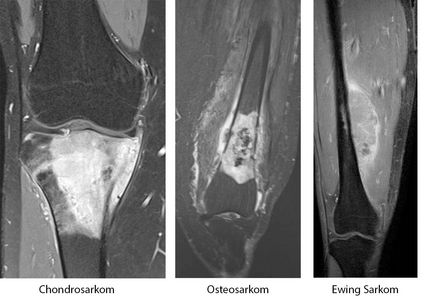

Es gibt viele verschiedene Arten von Weichteil- und Knochentumoren. Beim Knochen sind die drei häufigsten bösartigen Formen das Osteosarkom, das Chondrosarkom sowie das Ewing Sarkom. Bei den Weichteilen gilt das Liposarkom (im Fettgewebe) als häufigtste Tumorart. Jede Tumorart bedingt eine individuelle Behandlung.